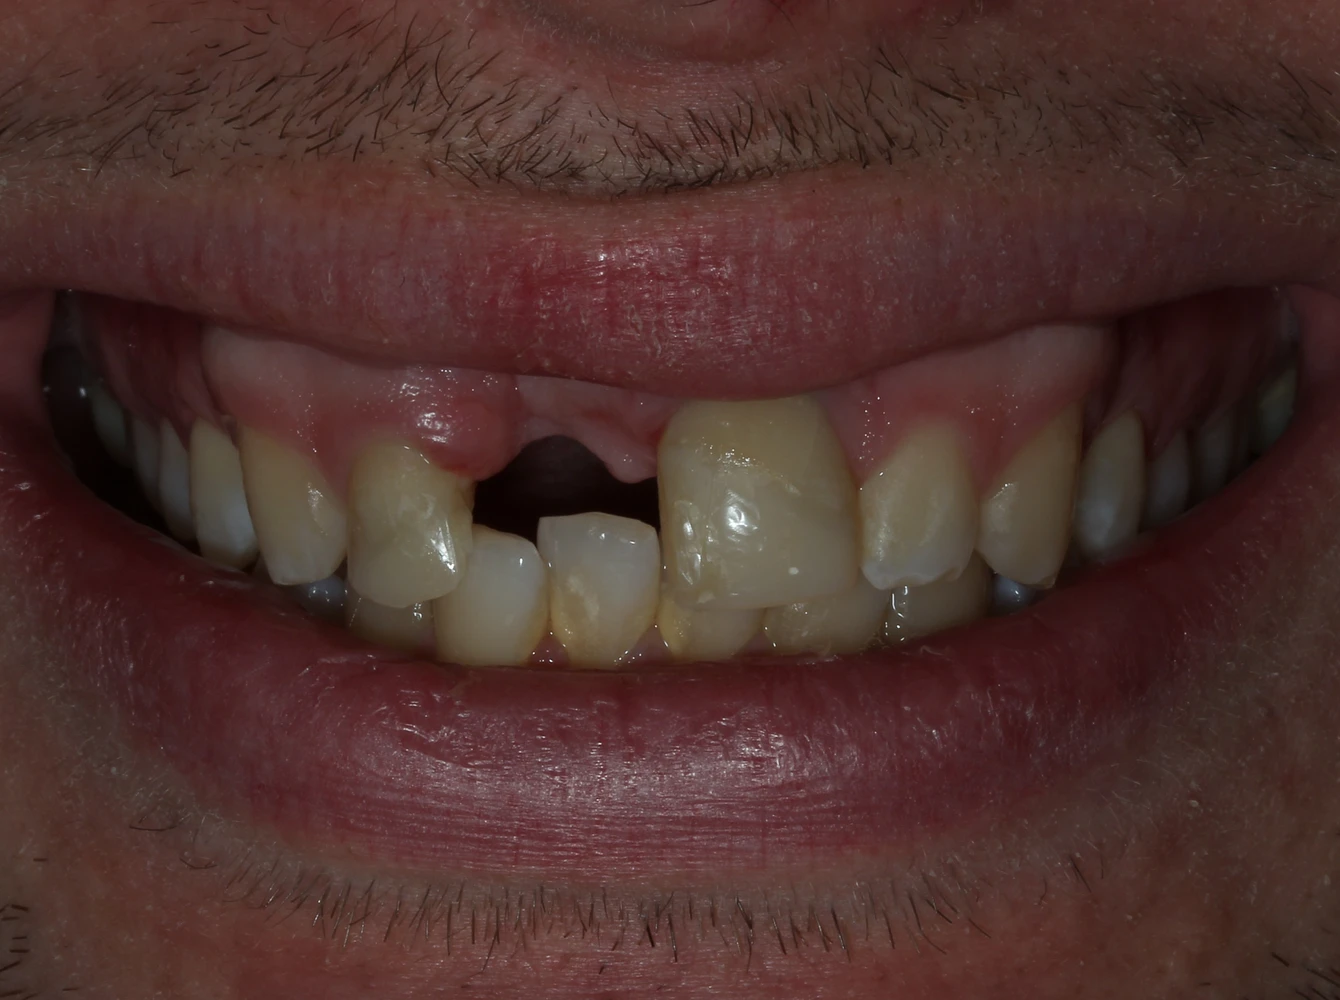

Diagnosticul inițial

Pierderea incisivului frontal

Traumatism dentar cu avulsia completă a dintelui 21

Defect osos alveolar

Resorbție osoasă moderată în zona edentată

Impact estetic și funcțional

Dificultăți fonetice și disconfort estetic marcat

Alexei, un tânăr energic și activ, a suferit un accident în timpul unei vacanțe cu prietenii, în urma căruia a pierdut un incisiv superior central. Pe lângă impactul estetic major, trauma a dus și la pierdere de volum osos și gingival în zona afectată, ceea ce a făcut necesară o reabilitare implanto-protetică complexă.

Provocarea și obiective principale

Provocarea principală a fost reconstrucția naturală a zonei frontale cu integrare estetică perfectă în arcada dentară existentă.